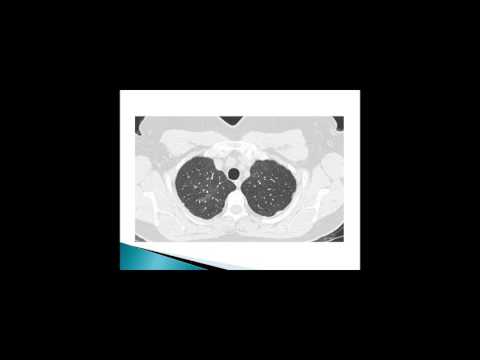

Entrevista EPID en las enfermedades del tejido conectivo – Dr Fabian Caro

EPID en las enfermedades del tejido conectivo Diagnóstico y Tratamiento Oportuno - Dr Fabián Caro